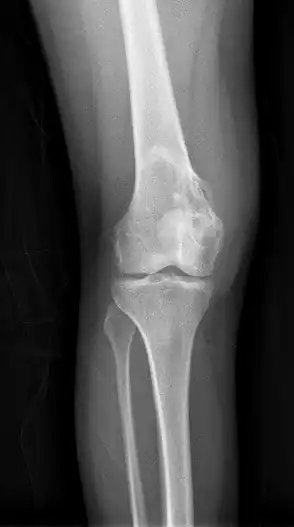

| Osteochondroma, a common type of non-cancerous chondrogenic tumors | |

| Chondroblastoma[2] | ![]() | |